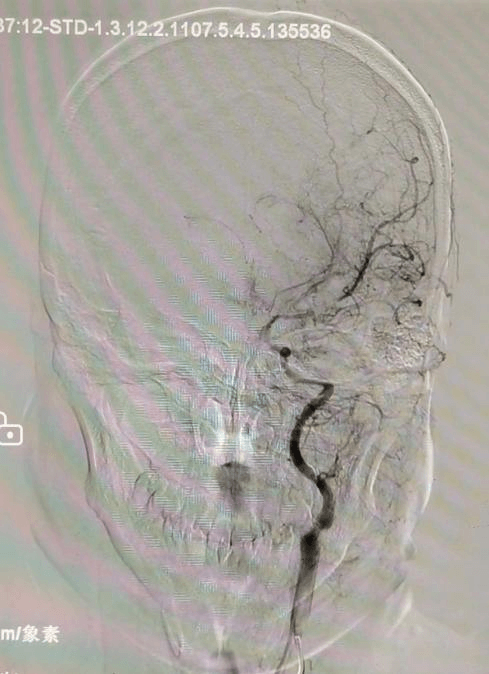

硬脑膜动静脉瘘患者同样在个性化方案中重获新生。患者因反复头晕,在外院怀疑静脉畸形,来到东方总院后,脑血管造影明确为硬脑膜动静脉瘘。通过详细的沟通,家属选择介入栓塞,吴全主任团队采用介入打胶栓塞的治疗方式,精准地堵住异常血管,一次性完全栓塞,术后患者头晕症状消失,生活质量大幅提升。